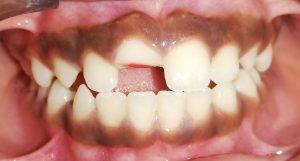

We at the Department of Pediatric & Preventive Dentistry focus on comprehensive oral health care needs of a child from infancy to adulthood and provide comprehensive, therapeutic as well as preventive care to all children including those with special care needs.

Treatment and Services